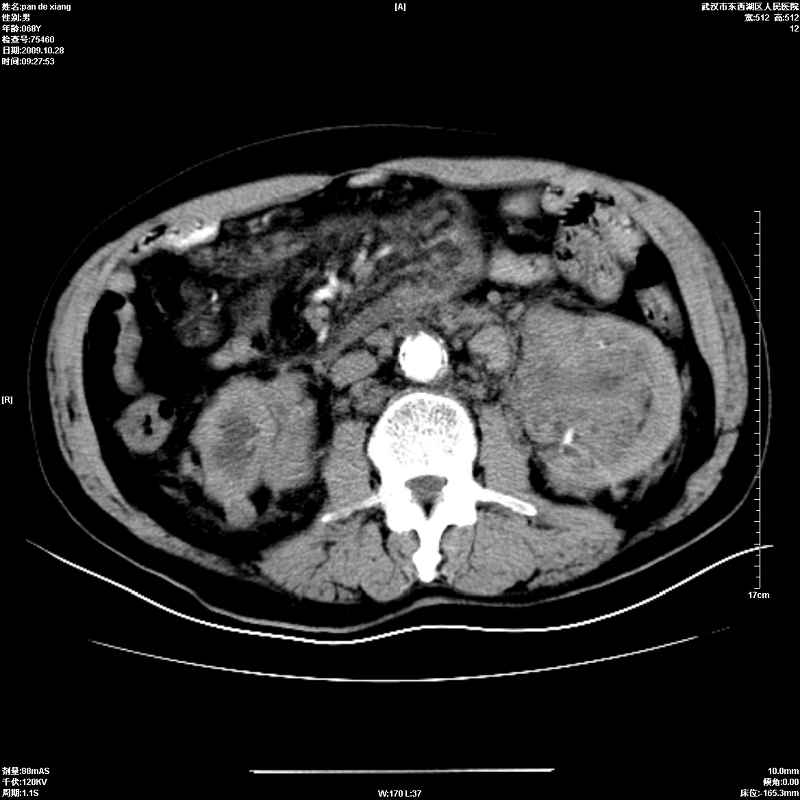

以下是引用杀毒软件在2009-10-28 20:41:00的发言:[br]结合临床考虑---白血病双肾改变或淋巴瘤。

以下是引用zxl51642在2009-10-29 9:59:00的发言:[br]结合临床“单克隆免疫球蛋白血症”,考虑双肾为继发损害并肾功能不全(尿中大量igg及少量iga、igm等大分子免疫球蛋白滤出所致继发损害),椎前软组织肿块为髓外造血。与浆细胞瘤有区别,平扫时有战友说的很清楚。